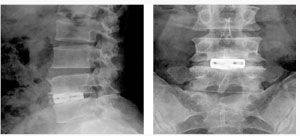

척추관 협착증의 방사선 소견

후방 요추체간 유합술 (PLIF) : 광범위한 후방 감압술 후 추간판(디스크)을 제거한 후 골이식을 시행하여 추체간 유합을 얻는 것

- 후외방 유합술에 비해 절개가 적다

- 신경근에 대한 충분한 감압이 이루어진다

- 추간판(디스크)로 인한 동통 및 재발이 없다

- 추간판 높이를 정상으로 회복시켜 준다

- 척추 정렬을 정상으로 회복시켜 준다

* 현재에는 최소 침습적인 방법으로 적은 절개를 통해 가능하다